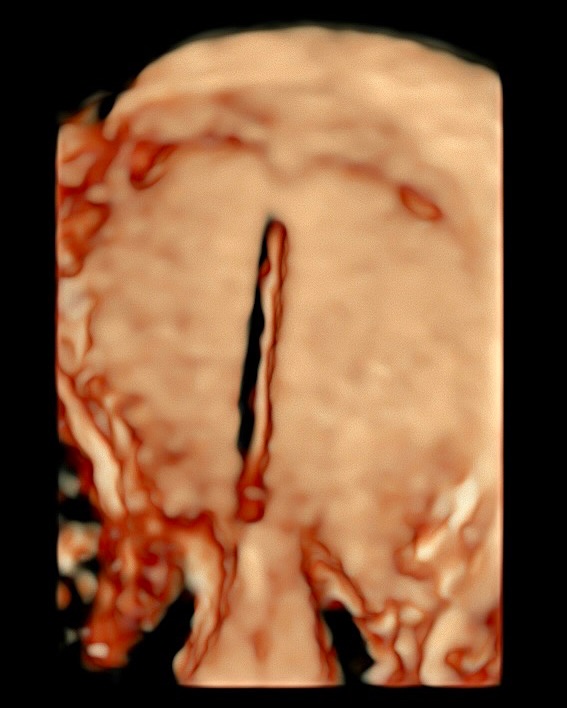

A ultrassonografia em três dimensões (3D) revolucionou a forma como avaliamos o útero e seu interior. Sua capacidade de gerar imagens volumétricas permite uma análise detalhada da cavidade endometrial, com cortes multiplanares que ampliam nossa percepção anatômica e funcional.

- Patologias endometriais, como pólipos, miomas submucosos, sinéquias e malformações uterinas, podem ser visualizadas com mais clareza na ultrassonografia 3D, facilitando o diagnóstico precoce e contribuindo para o planejamento terapêutico mais eficaz.

-  Quando falamos em dispositivo intrauterino (DIU), a avaliação 3D é especialmente útil. A reconstrução volumétrica permite verificar com precisão o posicionamento do DIU, identificando deslocamentos, inserções parciais ou até perfurações, muitas vezes imperceptíveis em exames bidimensionais convencionais.